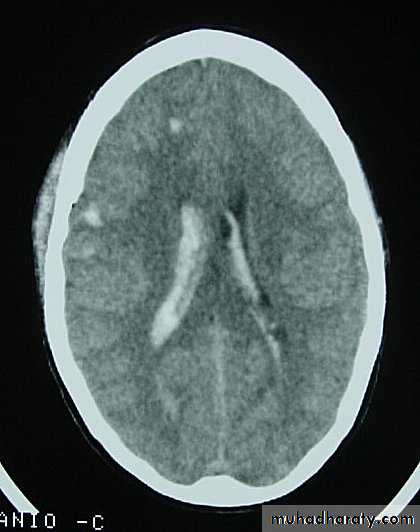

They can increase both brain metabolism and blood flow, therefore increasing intracranial pressure.5. Hydrocephalus

a. Acutely due to obstruction of CSF outflow due to intraventricular blood.b. Delayed post-traumatic communicating hydrocephalus due to impaired CSF reabsorption following traumatic subarachnoid haemorrhage

Intraventricular blood can lead to Hydrocephalus